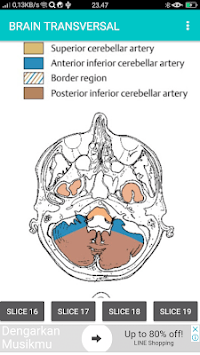

SECTIONAL ANATOMY MRI

POCKET ATLAS MRI is developed by Multirez and is available for free on the Google Play Store. POCKET ATLAS MRI has 5000 installations so far, with a required Android version of 4.0 and up. SECTIONAL ANATOMY MRI

Screenshots